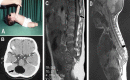

Figure 7

Images showing: A) a 9-year-old girl presenting with a remarkable hair tuft at the back above the gluteal fold; B) the left foot was smaller, had equinus posture, and showed spontaneously upgoing big toe; C) sagittal T2-weighted MRI showed features of diastematomyelia with thinning of the spinal cord (large arrow) resulting from the intervening subarachnoid space between the 2 hemicords. There is also remarkable widening of the spinal canal with tethering of the cord (small arrow). D-F) serial axial T-2 weighted images revealed that the spinal cord started to divide at the level of L2 (E) into 2 halves (F).